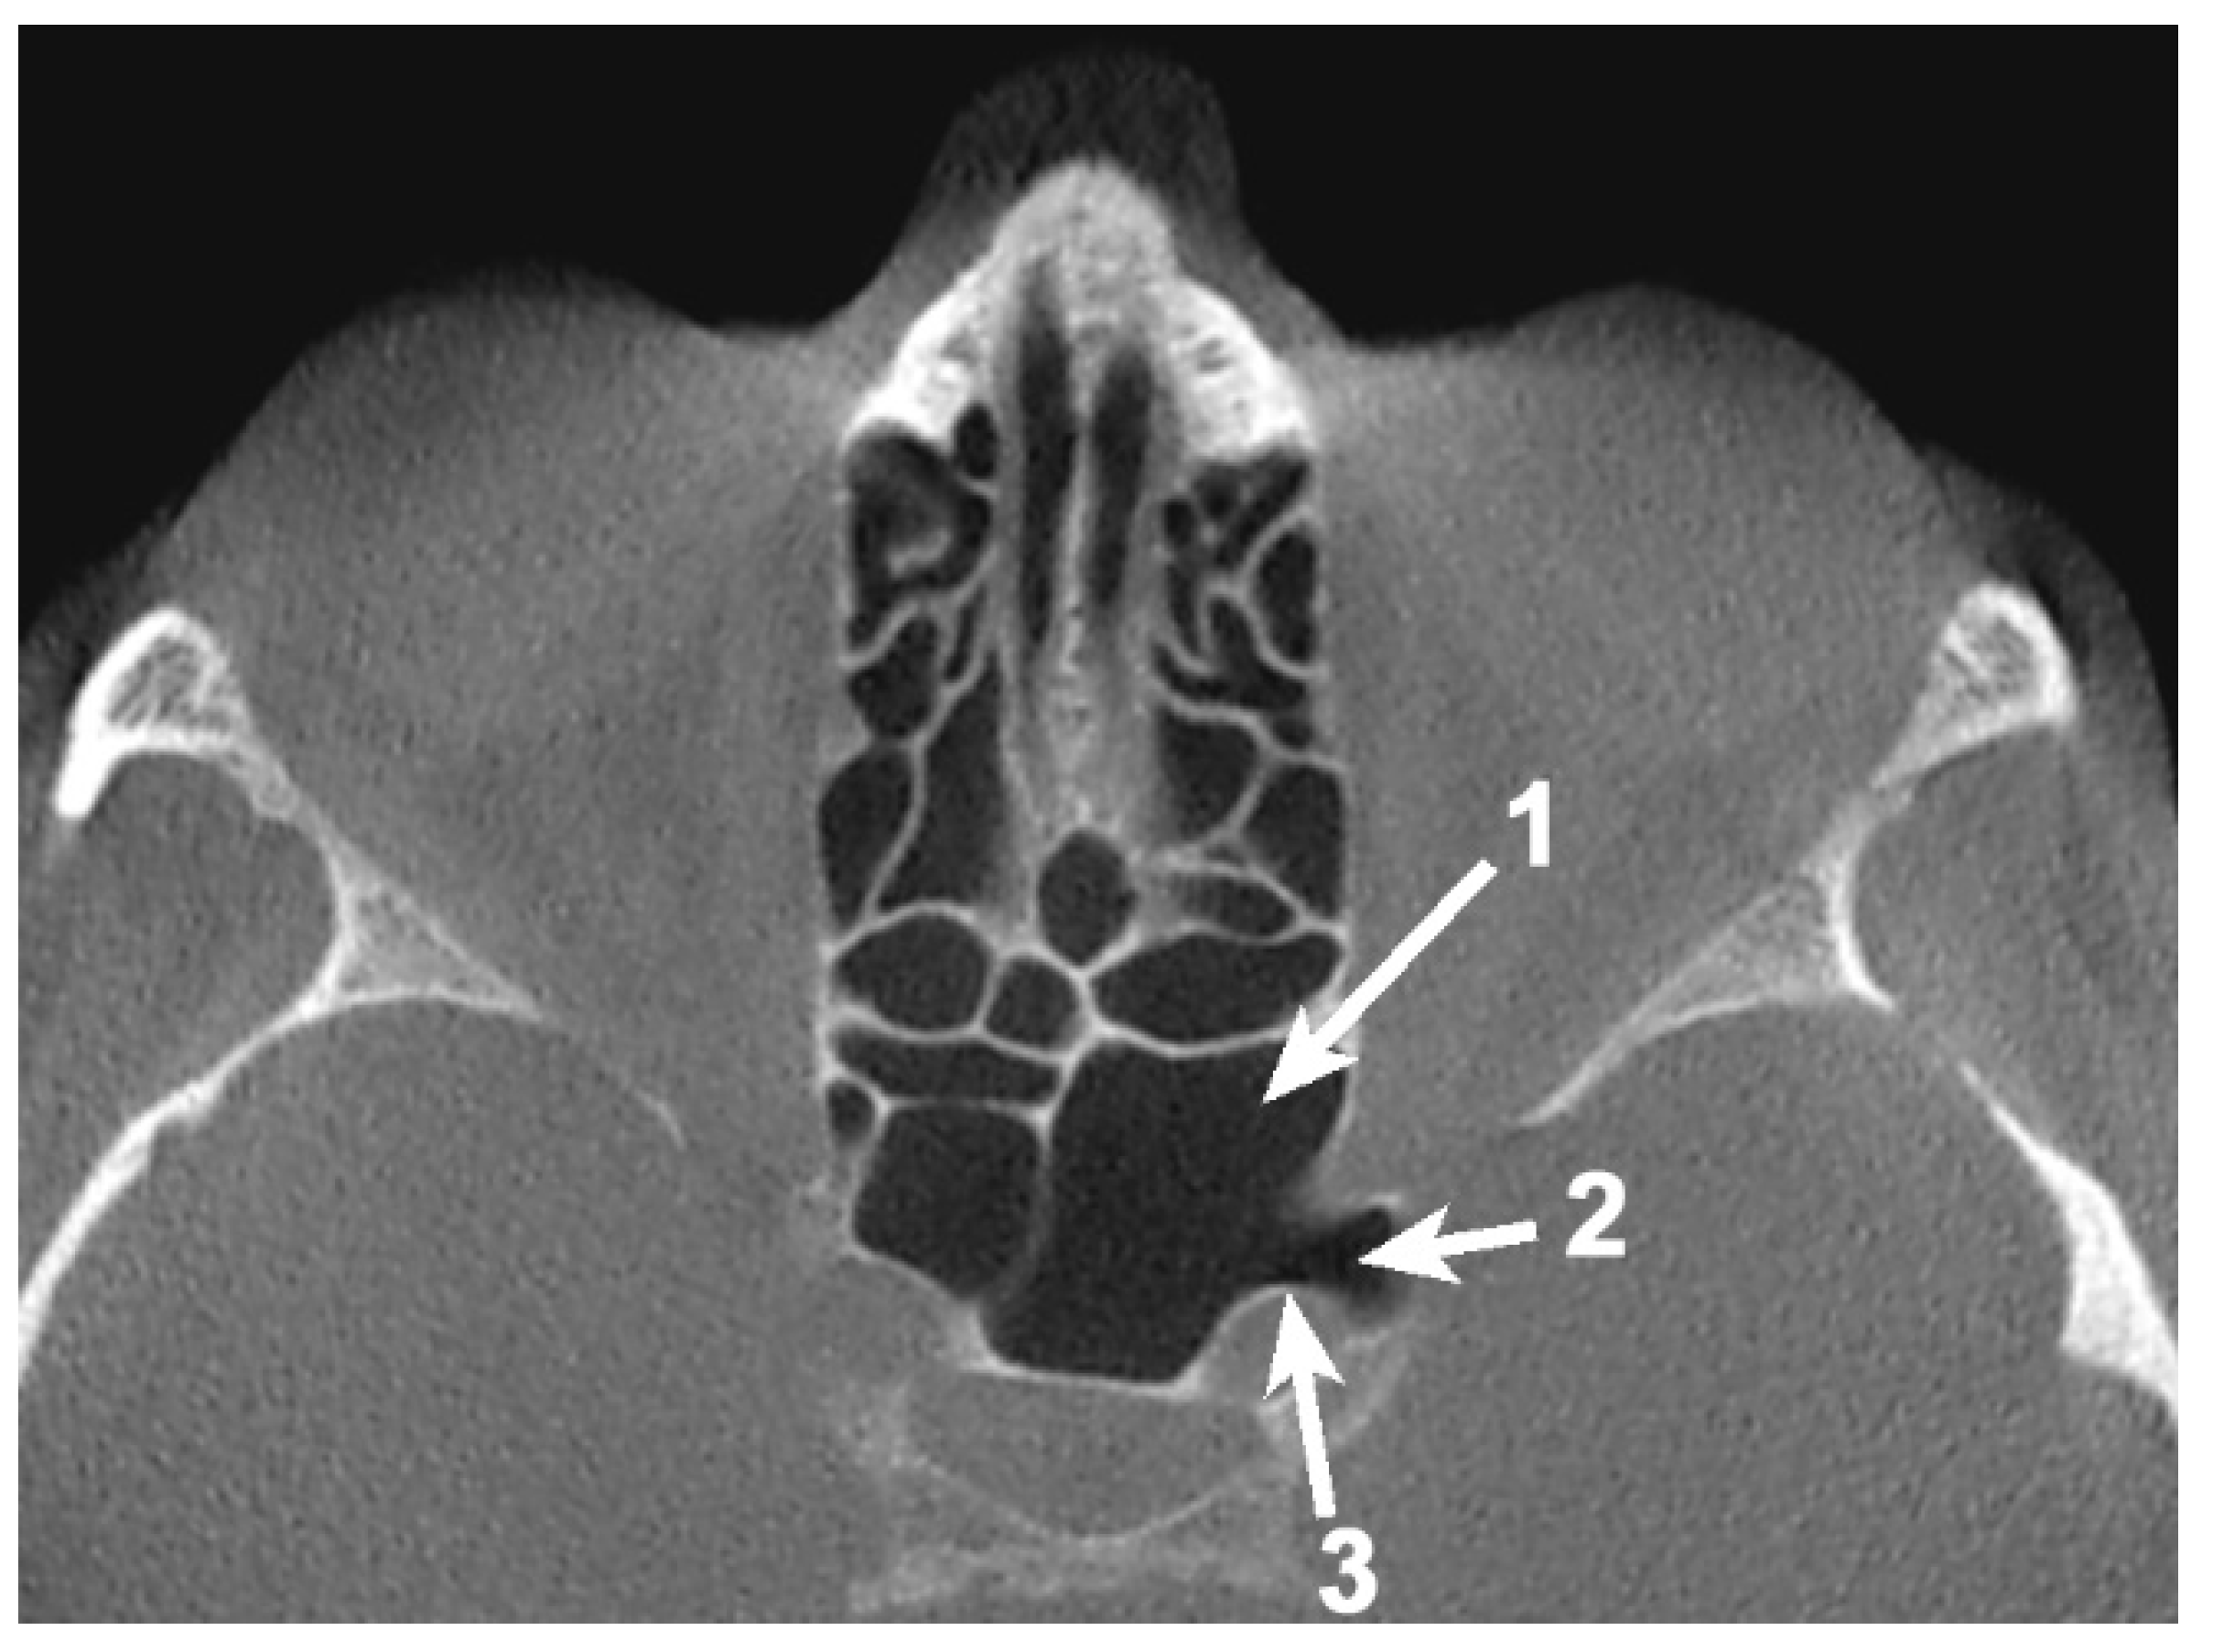

Simultaneous pneumatization of both LSW roots was noted in 31 cases (38.75%) and 43 sides (26.87%) (Table 2; Figure 3). This kind of extensive pneumatization was more frequent in the female group (22 cases, 71%).

Five (16.13%) out of the 31 cases with pneumatization of both LSW roots presented combined pneumatization. If, for the other cases, the origin came either from PEAC (non-ONC/ ONC) or the sphenoid sinus, in these 5 cases, the simultaneous pneumatization occurred from separated origins for each of the two (Figure 3). Two of these patients presented the ONC extending into the OS and the sphenoidal sinus within AR, and the other three cases presented ONC pneumatization extended within the AR and the sphenoidal sinus with a recess within the OS.

Figure 3. Bilateral sagittal CBCT reconstruction, demonstrating the pattern of pneumatization of both the optic strut (OS) and anterior root (AR). (a) Left side; (b) Right side: 1. Pneumatized AR; 2. Pneumatized OS; 3. Onodi cell; 4. Sphenoid sinus.